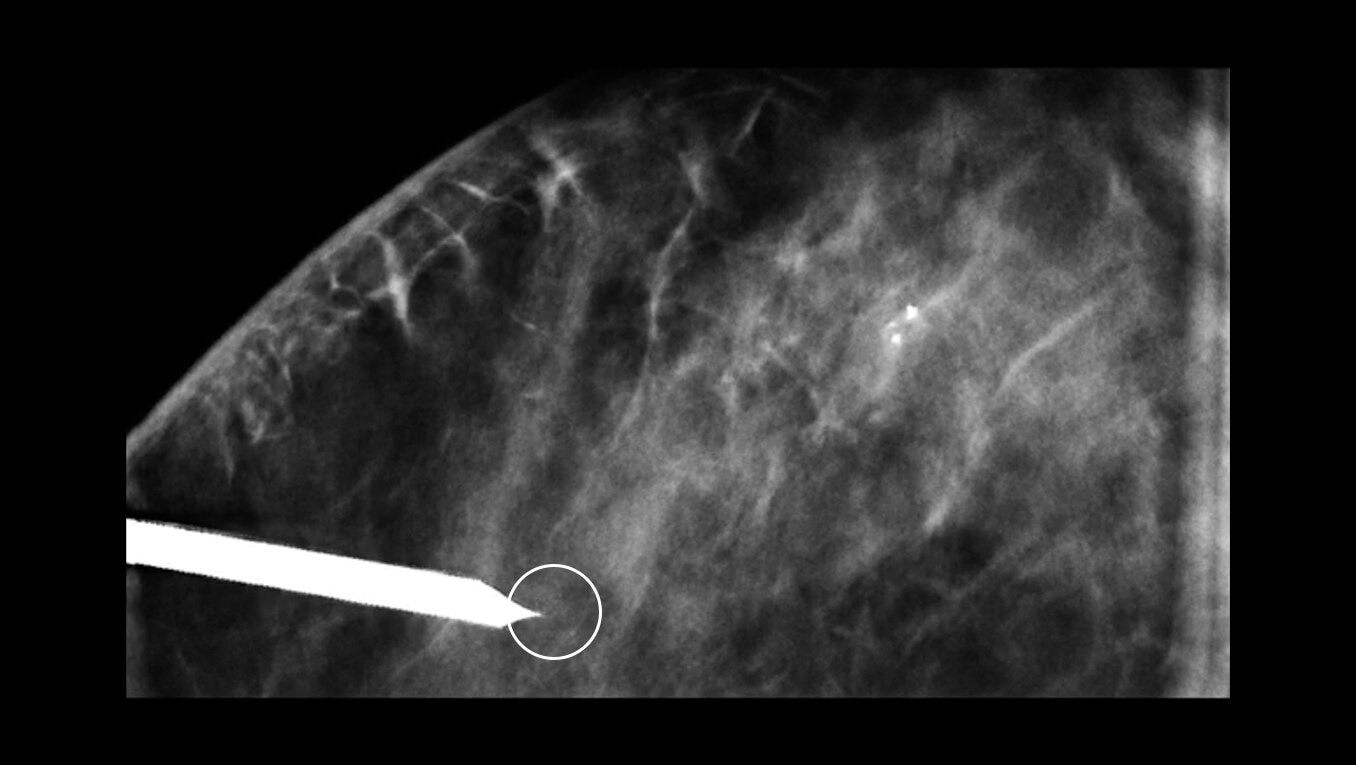

Enabling fast and accurate breast biopsies

Pristina Serena provides the option to access the breast with a newly designed side approach. The large working space simplifies patient positioning, reduces needle visibility to ease patient anxiety, and provides access to the most challenging lesions. All these biopsies can be performed in the same room as mammography screening—improving patient flow and center throughput.

Increase accuracy with precision targeting

Pinpoint incision entry for accurate needle placement and anesthesia delivery around the incision site with our laser guide. The automatic mechanical stop also ensures that the needle halts when it reaches the target. Pristina Serena is a biopsy system that can be moved away during the procedure to keep the needle out of the field of view so it doesn’t alter images.